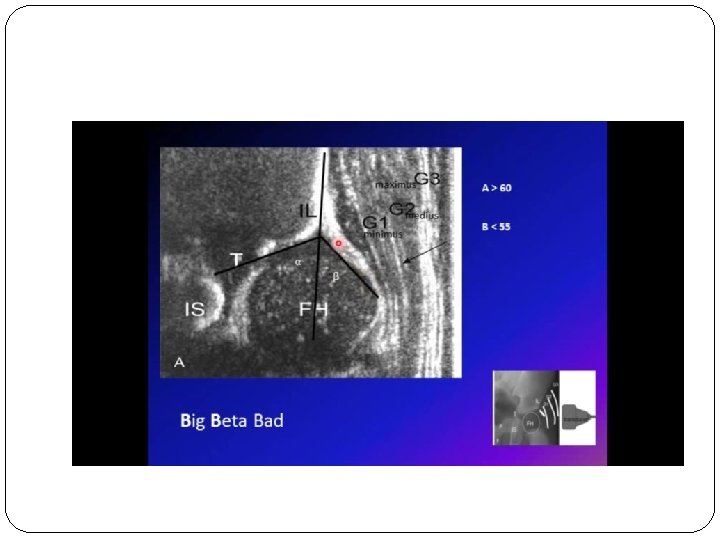

Invetigation : 1)U/S

The triradiate cartilage is the 'Y'-shaped epiphyseal plate between the ilium, ischium and pubis to form the acetabulum of the hip bone.